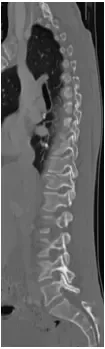

The fracture was stabilized by Minimal Invasive spine surgery with percutaneous pedicle screws in T11, 12 and L1 and rod fixation.

Patient tolerated the procedure well. She was pain free after the surgery and discharged home after 1 day. She was able to return to her usual activities in about 8 weeks.